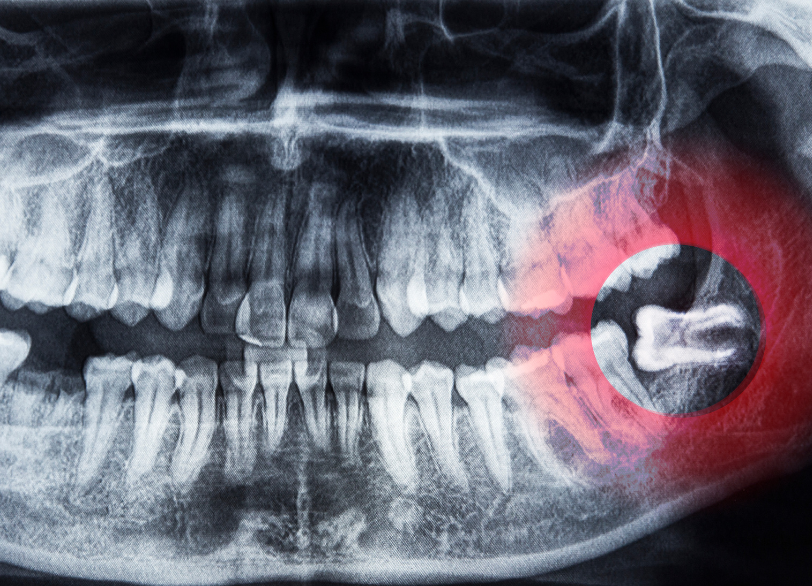

親知らずは専門的には「智歯(ちし)」や「第三大臼歯」と呼ばれ一番奥に最後に生えてくる永久歯です。

永久歯が生えそろう10代後半から20代前半頃に親も知らないうちに生えてくることから「親知らず」という名前がついたと言われています。

現代人は食生活の変化などから、昔の人に比べて顎の骨が小さくなる傾向にあります。

そのため最後に生えてくる親知らずがきれいに並ぶための十分なスペースがなく様々なトラブルの原因となってしまうことが非常に多いのです。

なぜ親知らずはトラブルを起こしやすいのでしょうか

スペースが足りないことで親知らずは私たちの予想もしないような生え方をすることがあります。

横や斜めに生えてくる

スペース不足のためまっすぐ上に出てくることができず、横向きや斜めに傾いて生えてきてしまうケースです。

隣にある大切な奥歯(第二大臼歯)をぐいぐいと押し続け、歯並び全体を乱してしまったり強い痛みの原因となったりします。

歯茎に埋まったまま(埋伏歯)

骨の中に完全に埋まったままだったり、頭の一部だけが歯茎から顔を出していたりするケースです。

中途半端に顔を出していると歯と歯茎の間に深い溝ができ、そこに汚れが溜まって歯茎がひどく腫れ上がる「智歯周囲炎」という炎症を繰り返し引き起こすことがあります。

また骨の中に埋まったままでも隣の歯の根を溶かしてしまったり、大きな袋(嚢胞)を作ってしまったりする原因となることもあります。